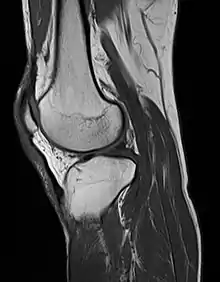

Magnetic resonance imaging

MRI uses strong magnetic fields to align atomic nuclei (usually hydrogen protons) within body tissues, then uses a radio signal to disturb the axis of rotation of these nuclei and observes the radio frequency signal generated as the nuclei return to their baseline states.[8] The radio signals are collected by small antennae, called coils, placed near the area of interest. An advantage of MRI is its ability to produce images in axial, coronal, sagittal and multiple oblique planes with equal ease. MRI scans give the best soft tissue contrast of all the imaging modalities. With advances in scanning speed and spatial resolution, and improvements in computer 3D algorithms and hardware, MRI has become an important tool in musculoskeletal radiology and neuroradiology.

One disadvantage is the patient has to hold still for long periods of time in a noisy, cramped space while the imaging is performed. Claustrophobia (fear of closed spaces) severe enough to terminate the MRI exam is reported in up to 5% of patients. Recent improvements in magnet design including stronger magnetic fields (3 teslas), shortening exam times, wider, shorter magnet bores and more open magnet designs, have brought some relief for claustrophobic patients. However, for magnets with equivalent field strengths, there is often a trade-off between image quality and open design. MRI has great benefit in imaging the brain, spine, and musculoskeletal system. The use of MRI is currently contraindicated for patients with pacemakers, cochlear implants, some indwelling medication pumps, certain types of cerebral aneurysm clips, metal fragments in the eyes and some metallic hardware due to the powerful magnetic fields and strong fluctuating radio signals to which the body is exposed. Areas of potential advancement include functional imaging, cardiovascular MRI, and MRI-guided therapy.